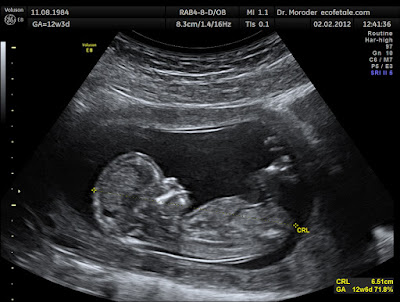

(Image: 12 Week Foetus in the Mother's Womb - Wikipedia)